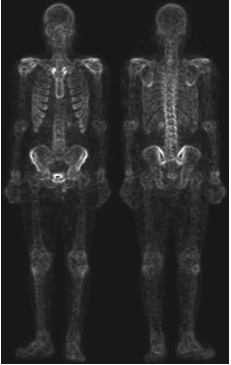

위의 사진은 뼈 감염이나 종양 같은 질환은 감지하는 전신 골격 원자력 스캔입니다. 디지털 영상 처리는 문제 지향형이기 때문에 어떤 문제를 가지느냐에 따라서 서로 다른 방향성을 가지게 됩니다. 저희는 사진에 있는 골격의 디테일을 살리는 것으로 하겠습니다. 지난 포스팅에서 따로 설명은 드리지 않았지만 라플라시안 필터는 영상의 세세한 디테일을 살리는 데 사용될 수 있으며 그래디언트 기반 필터링은 영상 내의 중요한 엣지를 찾아내는 데 도움을 줄 수 있습니다.

입력 영상 $I$에 라플라시안 필터를 적용하는 것은 라플라시안 필터를 이용한 영상 샤프닝의 시작이라고 하였습니다. 하지만 위의 그림을 보면 영상 내의 노이즈가 꽤 많이 있기 때문에 샤프닝된 영상은 노이즈가 많을 것이라고 예상할 수 있습니다.